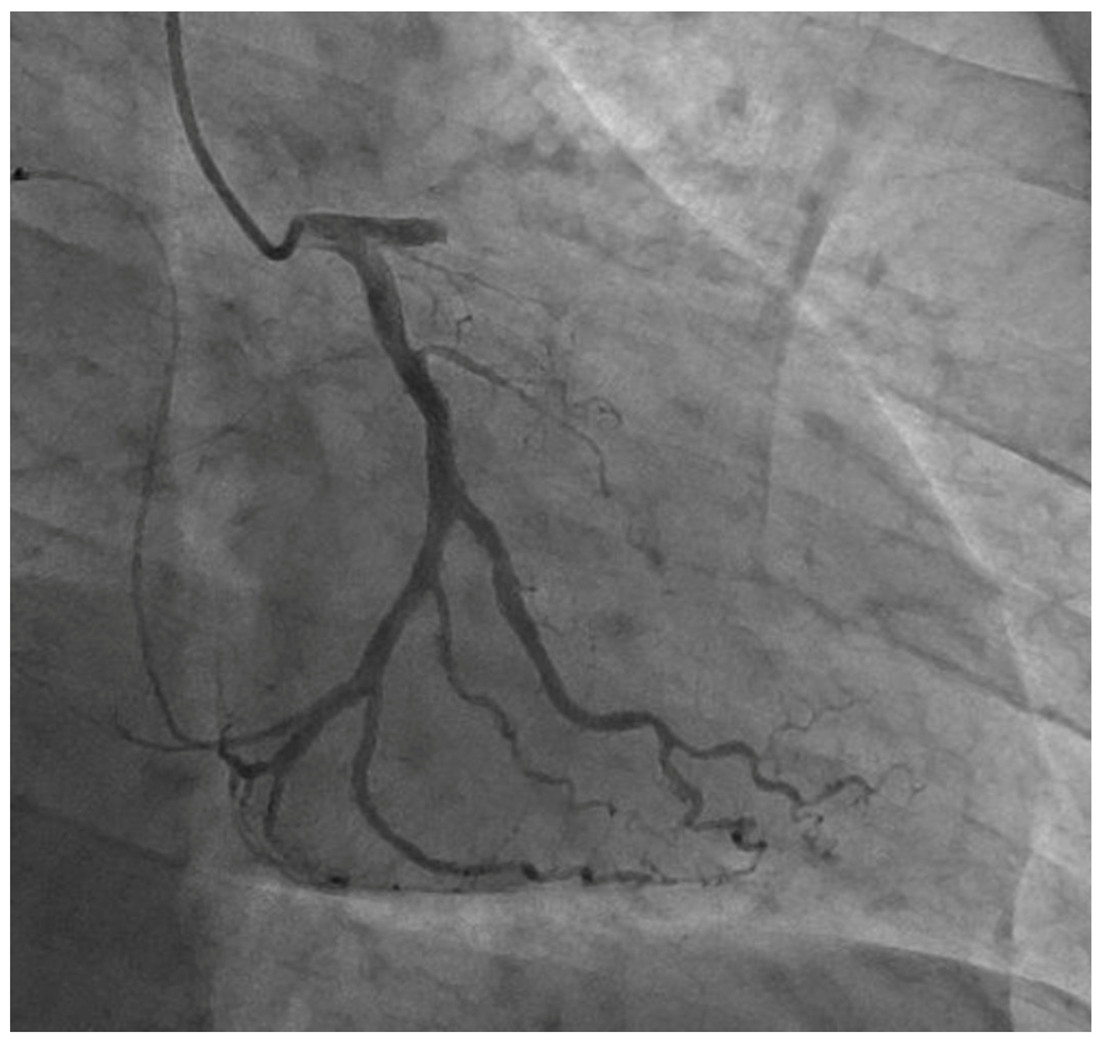

| 1. CAD | 26 (17.6) |

| (1) Asymptomatic CAD | 5 (3.4) |

| (2) Angina or equivalent | 17 (11.5) |

| (3) Myocardial infarction | 4 (2.7) |